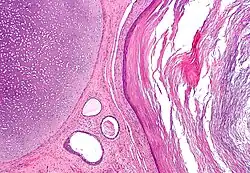

The endoderm is one of the germ layers formed during animal embryonic development. Cells migrating inward along the archenteron form the inner layer of the gastrula, which develops into the endoderm.

The endoderm consists at first of flattened cells, which subsequently become columnar. It forms the epithelial lining of the whole of the digestive tract except part of the mouth and pharynx and the terminal part of the rectum (which are lined by involutions of the ectoderm). It also forms the lining cells of all the glands which open into the digestive tract, including those of the liver and pancreas; the epithelium of the auditory tube and tympanic cavity; the trachea, bronchi, and alveoli of the lungs; the bladder and part of the urethra; and the follicle lining of the thyroid gland and thymus.